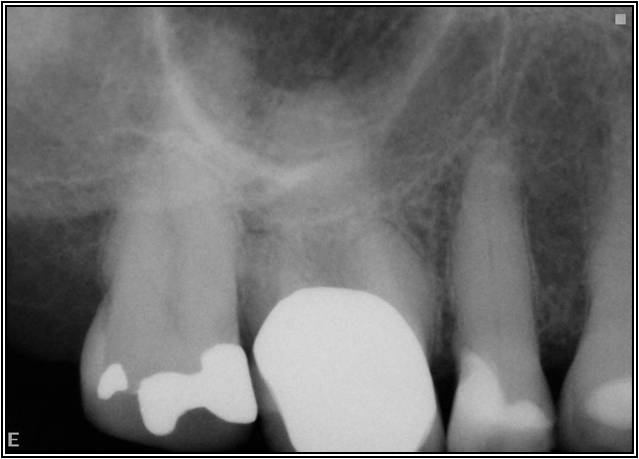

Excellent diagnosis essentially begins with two fundamental components: a doctor willing to listen to the patient’s chief complaint, and proper diagnostic tools. Among the most important tools are a precise periapical radiograph (PA) and bitewing (BW). Although a PA is often enough to provide an accurate portrayal of the patient’s condition, sometimes it alone does not suffice. Figure 1, Figure 2, and Figure 3 demonstrate a case that illustrates this point clearly. Despite two acceptable PAs (Figure 1 and Figure 2), it is difficult to assess the source of the patient’s pain to temperature. However, the BW radiograph Figure 3 provides significantly more clarity than either of the two PAs. The BW depicts localized bone loss (around tooth No. 2), a pulp stone (No. 2), a flat occlusion, numerous calcified canals, multiple restorations in tooth No. 30, and gross decay especially on tooth No. 3, which is the source of the patient’s pain to temperature. In this instance these images depict how much more useful a BW can be than just a conventional PA.

Fig 2. Acceptable PA radiograph.

Figure 2

Fig 3. BW of the same upper right area as shown in Figure 1 and Figure 2, depicting gross decay not visualized on prior PAs.

Figure 3